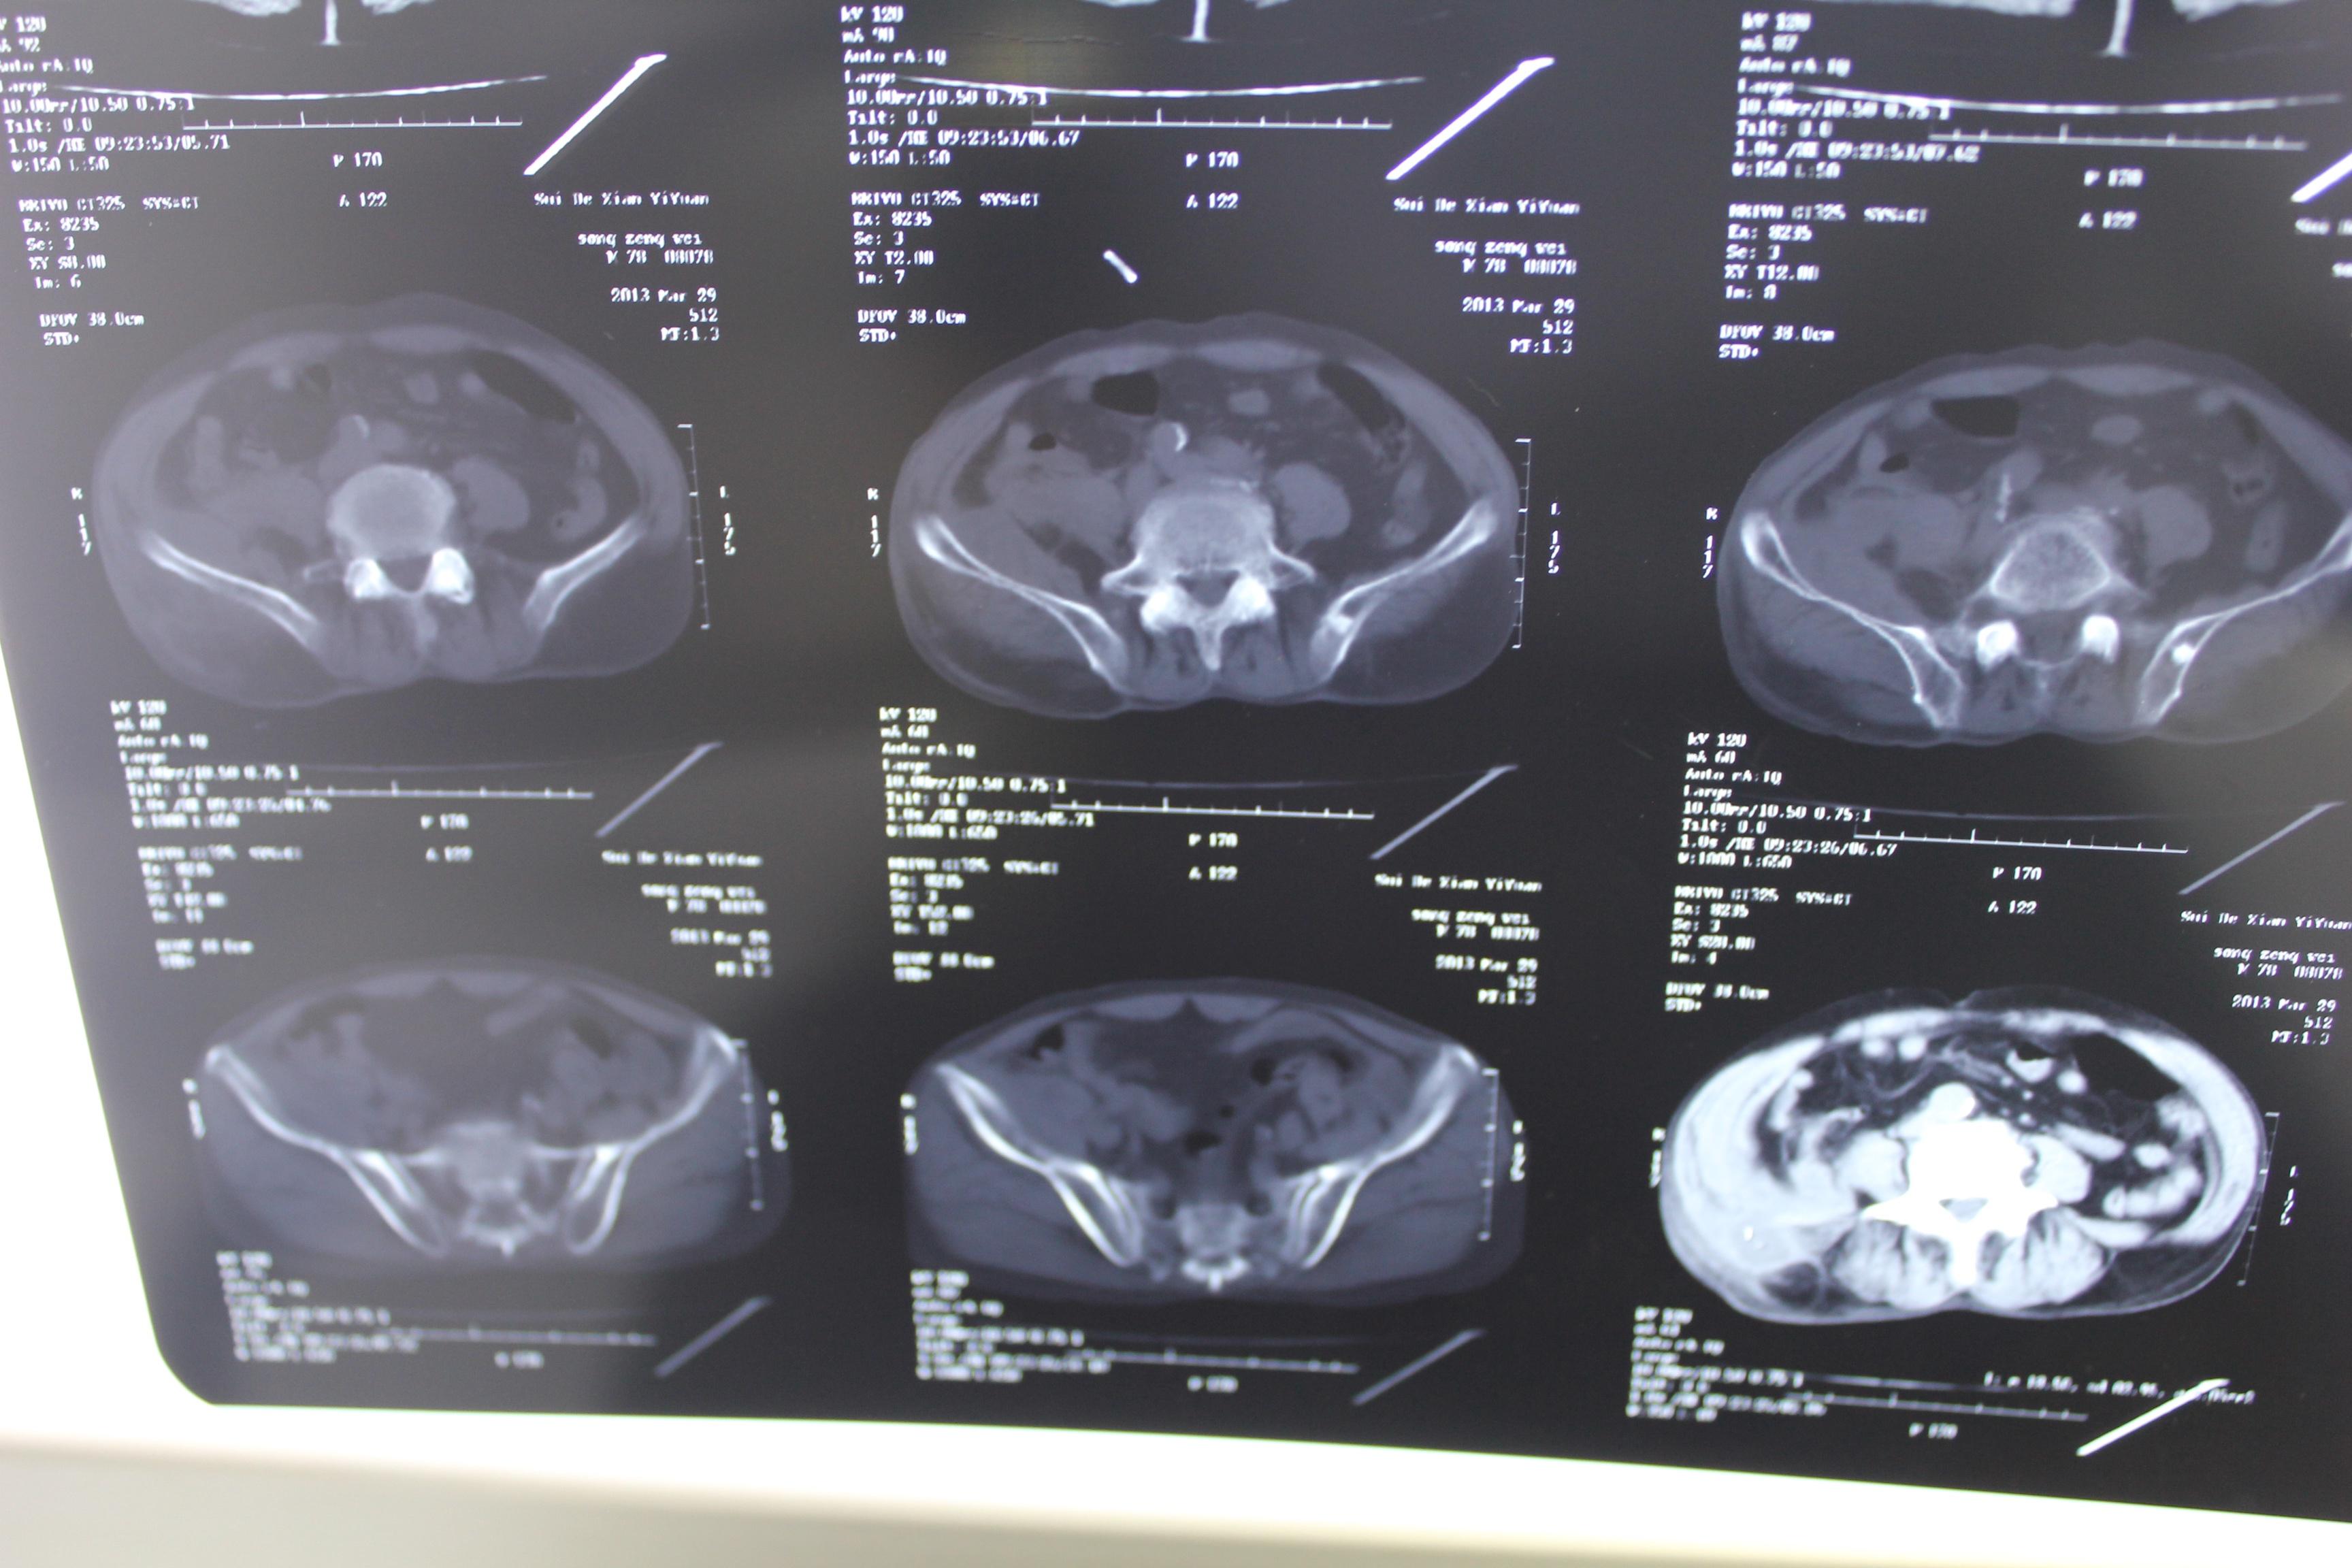

老年患者78岁,反复腰背部溃烂流脓4年,既往30年前曾在包块处排出蛔虫一条。CT: